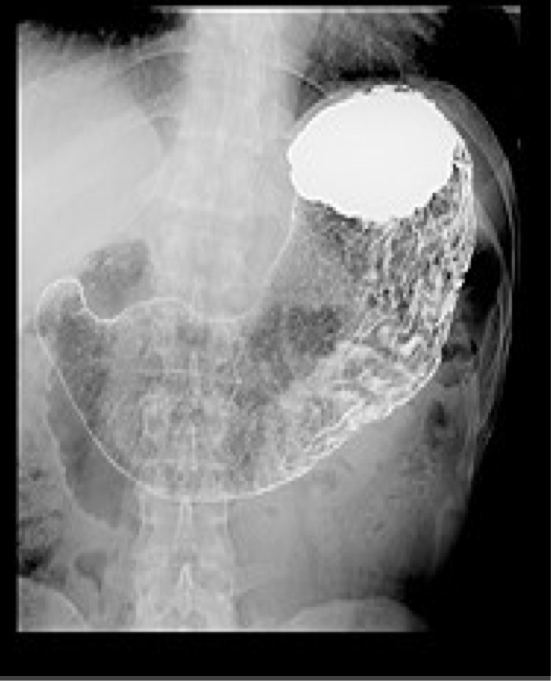

Upper GI (barium)

Evaluation of the esophagus, stomach, and duodenum using oral contrast.

Detect polyps, masses, malpositioned bowel, motility problems, GE reflux, and hiatal hernia